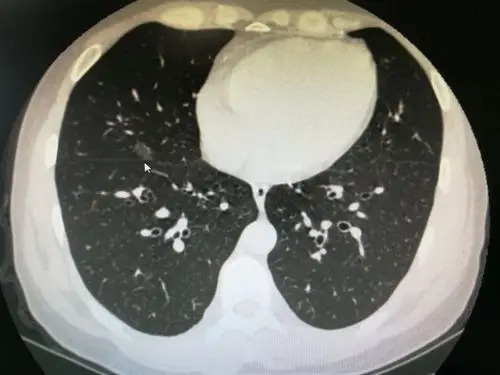

肺结节ct报告有这些描述千万要当心!1.分叶和毛刺;2.空泡 - 抖音

图文教你看懂恶性肺结节的ct表现

实性肺结节的良恶性ct征象解析

肺良恶性结节ct征象及鉴别诊断